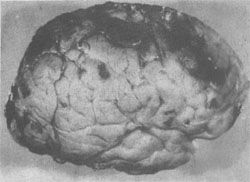

图16-19大脑前、中、后动脉供血区之间的C形边缘带示意图 【病理变化】 脑缺血的组织学变化在缺血12小时以后才较明显:神经元出现中央性Nissl小体溶解和坏死(红色神经元);髓鞘和轴突崩解;星形胶质细胞肿胀。1~2天出现脑水肿,中性粒细胞和巨噬细胞浸润,并开始出现泡沫细胞。第4天星形胶质细胞明显增生,出现修复反应。大约30天左右形成蜂窝状胶质瘢痕。 缺血性脑病的常见类型:①层状坏死。大脑皮质第3、5、6层神经元坏死、脱失、胶质化,引起皮质神经细胞层的中断。②海马硬化。海马锥体细胞损伤、脱失、胶质化。③边缘带梗死(图16-20)。梗死的范围与血压下降的程度和持续的时间有关,如血压持续下降,则梗死区自远心端向次远心端扩大,称为向心性发展(cardiopetal development),即C形梗死区向其两侧扩大,并自大脑顶部向颅底发展。大脑缺血性脑病边缘带梗死的极端情况是全大脑的梗死,但脑干的各核团由于对缺血(氧)的敏感性较低仍可存活。患者靠呼吸器以维持生命,但意识丧失,成为植物人。如何处置这样的病人则成为目前医学伦理学和医疗实践的难题。一旦这种病人死亡,其大脑乃成为由脑膜包裹,秽暗无结构的坏死组织,称为呼吸器脑。

图16-20 大脑缺血性脑病 大脑前、中、后动脉血供边缘带出血性梗死灶呈C形 综上所述,缺血性脑病的临床表现因缺血的严重程度和持续时间而异,轻者仅发现一过性精神错乱,或出现上肢肩带肌力和感觉减退,重者则可昏迷死亡。